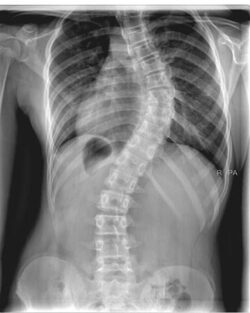

Scoliosis is when the spine curves sideways and twists, creating an “S” or “C” shape. The most common type is adolescent idiopathic scoliosis, meaning it appears during growth and has no known cause.

An x-ray is needed to confirm the diagnosis and to assess the extent of the curve(s). Doctors assess how advanced a scoliosis is by measuring the ‘Cobb angle’. A curve of 10° or more on an x-ray is considered scoliosis.